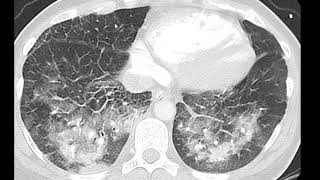

Observe aqui a retificação diafragma aquelas ondulações que são as inserções do diafragma aqui uma retificação também do diafragma melhor visualizado no perfil o perfil é excelente para visualizar as retificações do diafragma pois bem mas o melhor exame para se avaliar um efisema pulmonar é sem dúvida tomografia computadorizada com a janela de pulmão aqui é uma tomografia computadorizado normal numa janela de pulmão onde o pulmão fica com esse essa densidade esse cinza escuro veja o ar fica preto o ar dentro da traqueia preto o ar dentro dos bronquios preto e o pulmão esse cinza escuro que

é a média de densidade entre o ar e as paredes alveolares né e o interstício aí formado pelos septos alveolares paredes alveolares pelos alvéolos e os branquinhos aqui são os vasos cortados transversalmente e longitudinalmente essa aqui é uma uma tomografia normal no no enfisema pulmonar o exame que vai aparecer o exame de imagem que vai mostrar as primeiras alterações é a tomografia a radiografia só vai mostrar alterações já numa fase bastante avançada e que alterações seriam essas aqui uma tomografia de um enfisema pulmonar Então são áreas de redução da densidade áreas mais escuras veja aqui

na seta áreas de redução de densidade são as áreas do enfisema pulmonar parece ruído de traça pode ser adjacente a prea encostado na prea que é o enfisema parpal aqui pode ser na região central dos lóbulos que é o enfisema centrilobular Observe aqui múltiplos focos de enfisema múltiplas áreas de enfisema centrilobular entre eles pulmão normal o cinza aqui é pulmão normal as áreas mais escuras são áreas de enfisema e veja que no centro de cada área de enfisema há um pontinho que é uma artéria que é um que é uma artéria que corresponde a isso

aqui mostrado aí na lâmina né área de enfisema Cent lobular artérias aqui no centro e parênquima normal aqui ao redor então área de enfisema artéria e parênquima normal veja como a coisa tem uma boa correlação né tomografia tem uma excelente correlação com a histologia aqui no caso do enfisema pulmonar posteriormente eles vão se confluir aí se houver progressão e a destruição será maior então Aqui nós temos um pulmão com enema bastante avançado veja praticamente apenas áreas de enema sobrou pouco muito pouco de pulmão com densidade normal tudo escuro tudo áreas deema você veja que ainda

mantém as os vasos no centro de muitas áreas de enfisema Este é o enema Pan lobular ou panacinar pode ser pela confluência do centrilobular ou do centroacinar a evolução dele ou pode já iniciar como enfisema panlobular Principalmente nos casos de deficiência de Alfa 1 antitripsina mais um caso aqui de enfisema Pan lobular esse aqui provavelmente começou como enfisema centrilobular você veja que temos áreas de enfisema centrilobular que vão se confluindo e até formar aí um enfisema panlobular Esta é uma outra forma de enfisema o enfisema parasseptal veja que ele fica forma uma uma única fila

de imagens bolhosas adjacente a superfície do pulmão na coladas na pleura aí é o enfisema parasseptal veja que tem enfisema centrilobular também né então frequentemente eles andam junos fizemos a parpal com centro lobular quando cada imagem dessa ah passa fica igual a 1 cm ou maior que 1 cm pode ser chamado de bolha e aqui é uma situação mais grave mais avançada do enfisema parpal veja enfisema parpal com formação de de bolhas de grandes bolhas múltiplas bolhas aqui também tem efizema centrilobular enfisema parpal e formação de múltiplas grandes bolhas aí Alguns designam isso aqui como

enfisema bolhoso veja aqui um caso enfisema com grandes bolhas enfisematosas e que inclusive comprime o que sobra de parênquima normal então às vezes é necessário fazer a ressecção dessas bolhas para liberar o parênquima normal comprimido e aqui no raio x veja que a formação de grandes bolhas comprimindo o parênquima normal veja parênquima comprimido aqui e a forma ação de grandes bolhas nesse caso havia um nódulo também então aqui mostramos aspectos mais frequentes a aparência mais frequente do enfisema pulmonar na radiografia de tórax e na tomografia de tórax e gostaria de lembrar alguns detalhes primeiro que